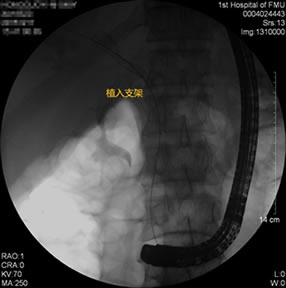

胃毕-Ⅱ术后球囊扩张狭窄胆管 胃毕-Ⅱ术后支架植入 胃毕-Ⅱ术后胆管胰管扩张

胃毕-Ⅱ术后胰管胆管双支架植入 胃毕-Ⅱ术后胆管金属支架植入